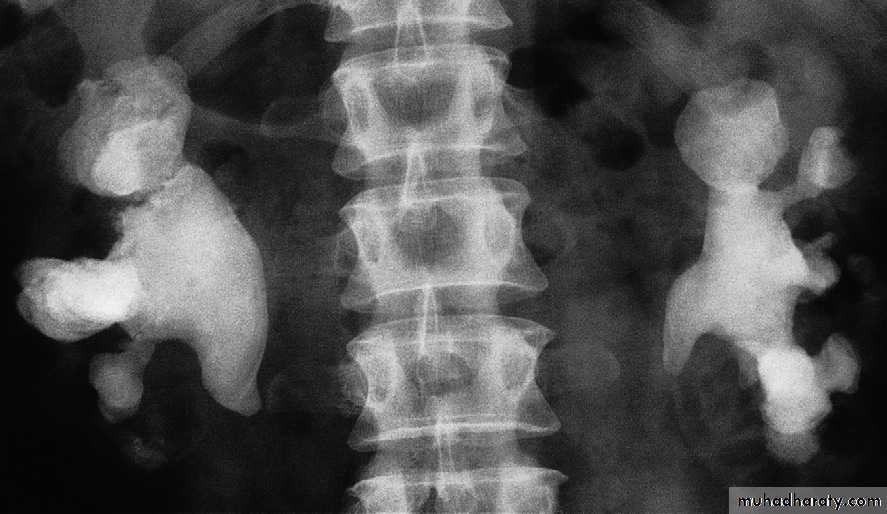

X-ray examinations :Most urinary calculi are calcified and show varying density. Many are uniformly calcifiedbut some, particularly bladder stones, may be laminated. Only pure uric acid and xanthine stones are radiolucent on plain radiography, but they can be identified at CT or ultrasound .Small renal calculi are often round or oval; the larger ones frequently assume the shape of the pelvicaliceal system and are known as staghorn calculi .

U/S :Most renal calculi of more than 5 mm in size are readily seen at ultrasound, produce intense echoes and cast acoustic shadows.